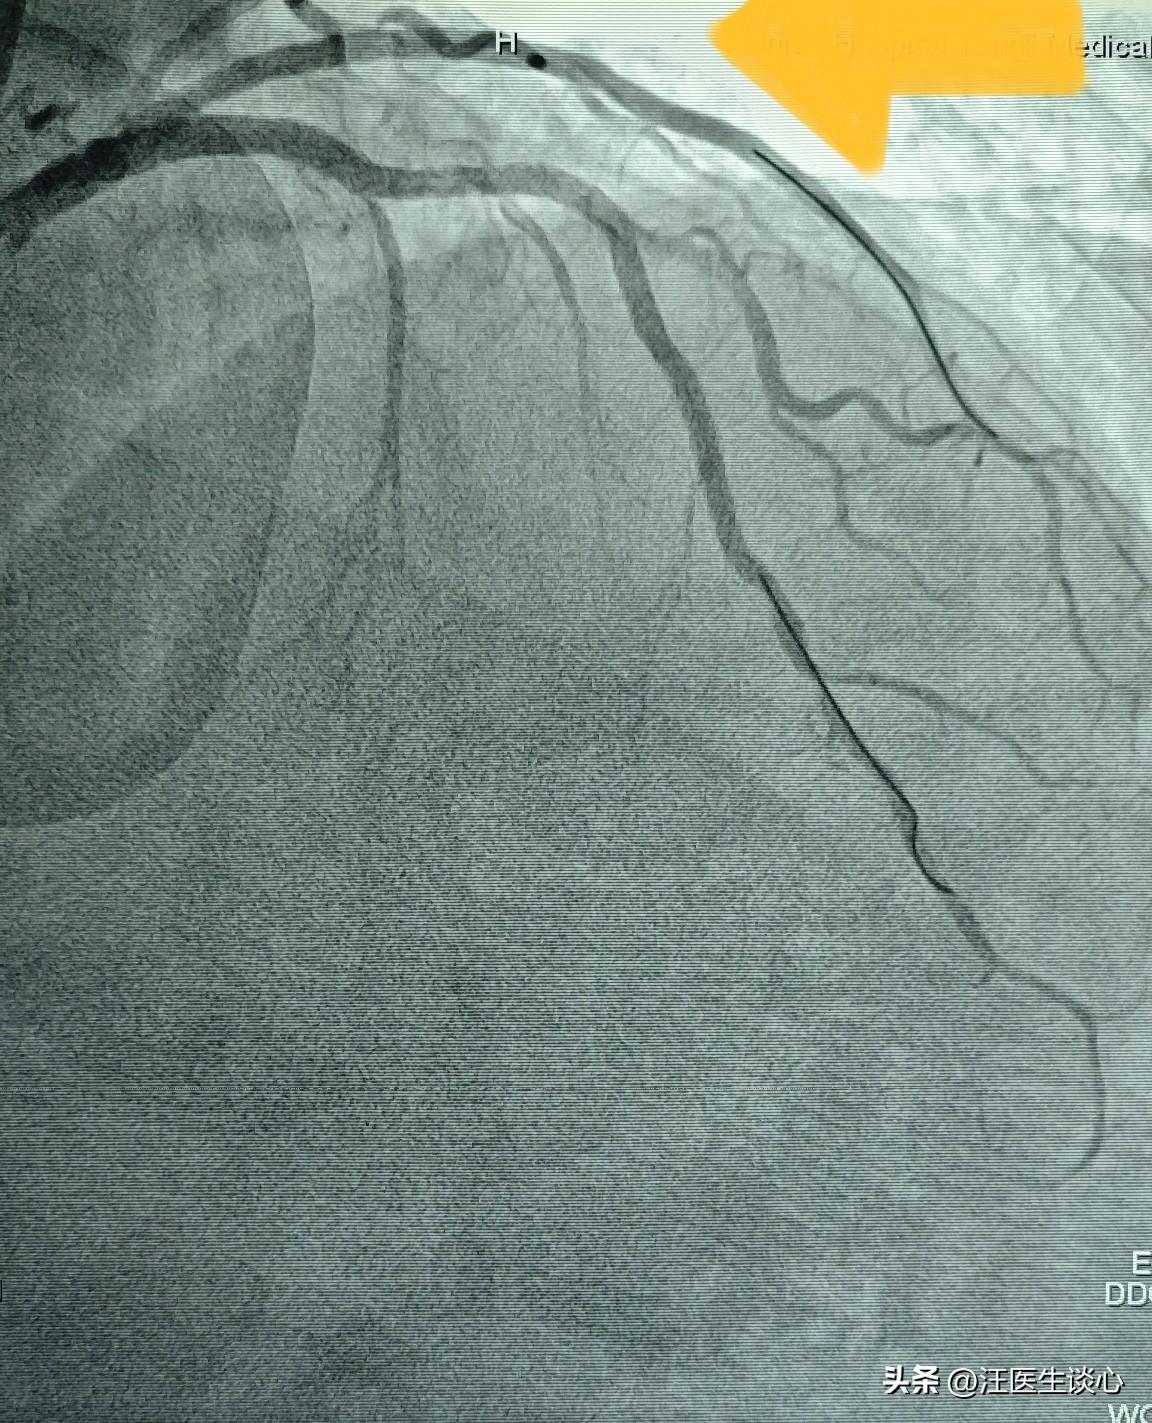

心脏血管太弯曲了,长支架过不去,只能做短的,三个变五个。 68岁男性患者因为冠心病在当地医院做了心脏造影,发现血管狭窄严重,血管呈多个S形弯曲,又有钙化,处理难度极大,就转过来治疗。 很多朋友对钙化可能不太了解。一般的血管它是有弹性的。而钙化的血管,血管壁就变得僵硬,血管壁本身是由富含弹力纤维的细胞组成。钙化以后就沉积了很多矿物质,血管就变得坚硬,像鸡蛋壳,像石头一样。直接做支架的话,在支架扩张的过程当中,血管因为缺乏弹性就会破裂,极其危险。再加上这个病人的血管弯弯曲曲的,长的支架很难通过。就像开着长长的大货车通过弯道一样,拐弯太急就无法通过。 针对这个患者,我们对这些坚硬的钙化斑块用切割球囊充分把斑块切开以后再扩张。长的支架无法通过这些弯曲的血管,于是放弃置入长的支架,改成多个短支架,串联覆盖整个病变区域。最终成功处理。